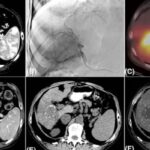

一名BRAF V600E突变且MSI-H的转移性结直肠癌患者,在接受维莫非尼、西妥昔单抗联合化疗后,竟实现了长达十年的完全缓解!这一罕见病例揭示了靶向联合治疗的巨大潜力。了解该方案的疗效、副作用及相关药物的购买渠道,为治疗带来新希望。 Read More... "十年完全缓解!靶向药维莫非尼如何攻克BRAF V600E突变结直肠癌?"